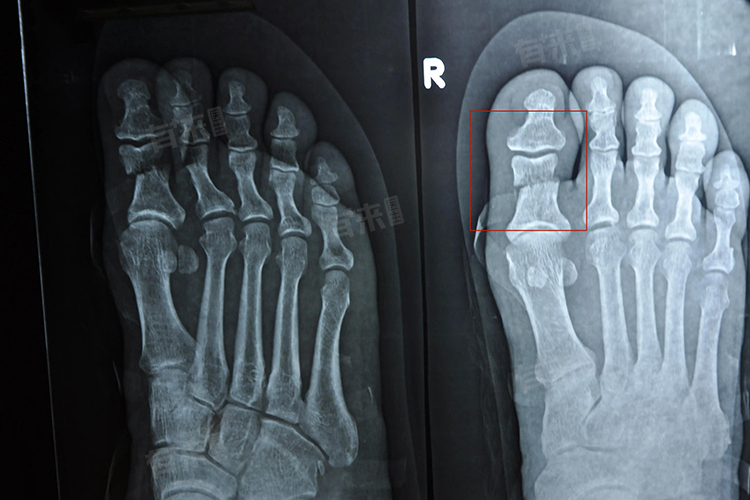

脚趾骨折恢复时间因骨折严重程度、个体差异等而有所不同,担责需要8-10周,长则需要3-8个月,甚至更长时间,恢复期间需遵循医嘱,注重康复锻炼与营养补充,以促进骨折愈合与功能恢复。

- 中度骨折:涉及较明显移位但未达到粉碎性骨折的程度,这类骨折需要手术切开复位并进行内固定,以确保骨折断端的准确对位和稳定,术后恢复时间较长,需要3-4个月来完成骨折的完全愈合。

- 重度骨折:特别是粉碎性骨折或伴有严重软组织损伤的骨折,恢复过程更为复杂和漫长,这类骨折可能需要手术内固定甚至截肢治疗,术后康复治疗和功能重建时间可能长达6-8个月,甚至更久。